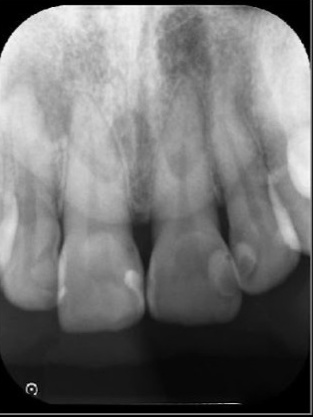

レントゲン検査を行って詳しく調べた結果、歯の根の先に歯の頭と同程度の大きさの根尖病巣(こんせんびょうそう)が確認できました。

根尖病巣とは歯の根の先にできる膿の袋のような病変です。

歯の内部の神経や血管が通る細い管に細菌感染が起こり、その影響が根の先に広がることで生じます。

治療終了から2年後のレントゲン画像です。根尖病巣が改善しています。